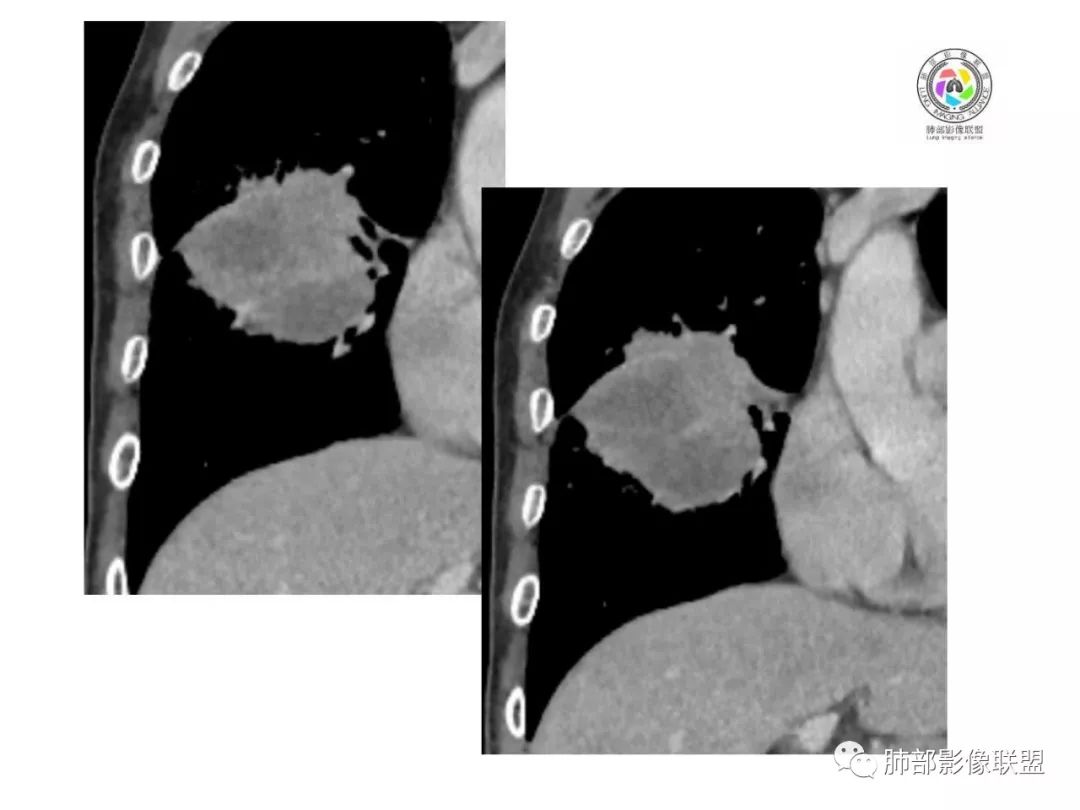

胸CT:右肺中叶实性占位性病变,呈膨胀性生长,对斜裂明显挤压,右肺中叶外侧段阻塞,并在边缘可见分叶、毛刺、棘突样改变,胸膜牵拉;增强可见病灶明显强化,可见边缘模糊血管影,病灶内可见大片状低密度区,隆突下可见肿大淋巴结。

诊断考虑:恶性病变。

右肺跨上叶与中叶一实性肿块影,中叶外侧段支气管堵塞,肿块有明显分叶、毛刺、棘突样改变,胸膜牵拉,周围有小花小草;增强可见病灶明显强化,病灶内可见大片状低密度区,以外侧为主,隆突下可见肿大淋巴结,恶性,考虑鳞癌可能。 医学百科网 | YxBaike.Com

老年男性,右肺不规则跨叶肿块,有分叶,相邻支气管阻断,强化不均有低密度坏死区,坏死区边界较清,类似湖泊样,内见血管穿行,造影征,病灶远端可能有阻塞性炎症,总体考虑鳞癌。

患者中老年男性,体检发现右肺占位。血常规轻度贫血,AFP、CEA正常,肝肾功能、血糖、血脂、心肌酶、电解质正常。胸部CT:右肺中叶巨大肿块灶,垮叶生长,可见分叶、毛刺、血管集束、支气管截断征象,远端周围可见小叶间隔增厚,增强轻度强化,内可见低密度坏死区,综合淋巴结肿大,且可见淋巴结内似低密度灶。综合考虑恶性,鳞癌并癌性淋巴管炎可能大。鉴别结核、腺癌。 医学百科网 | YxBaike.Com

胸CT:右肺中叶团块样实性占位,边缘膨隆,中叶外侧段阻塞,病灶可见深分叶、棘突,胸膜牵拉;增强不均匀强化,可见边缘模糊血管影,病灶内大片状低密度区,纵隔多发肿大淋巴结。

诊断考虑:恶性病变,鳞?大细胞?鉴别:TB

右肺中叶巨大肿块,外侧段近端支气管截断,横跨上中下三叶,主体在中叶,膨隆分叶,毛刺,网格,淋巴结大,不均匀强化,伴阻塞性肺炎及肺不张,湖泊样坏死,考虑恶性,鳞癌可能性较大

右肺中叶肿块影,向上向下侵犯叶间裂,边缘膨隆,分叶,毛刺。肿块内部密度不均,大片坏死。血管走形尚可。中叶支气管狭窄截断。增强不均匀强化。纵隔淋巴结肿大,部分融合。 医学百科网 | YxBaike.Com

考虑恶性,腺癌>鳞癌。鉴别炎肌母。 医学百科网 | YxBaike.Com

影像表现缺乏特异性,CT最常见的表现是位于周围肺野的实质性肿块,病变部位以上叶多见,常位于胸膜下;

1.具有肉瘤的特性:肿瘤体积一般较大,直径约大于5cm,边缘清楚、光整,由于肿瘤生长迅速,可见大片坏死,坏死边界清楚;常见支气管推移。

2.具有癌些特性:如分叶、短毛刺、空洞,但是钙化及胸膜凹陷征少见,病灶往往是直接侵犯胸膜,可以远处转移,肺门及纵隔淋巴结可明显肿大; 医学百科网 | YxBaike.Com

3.强化方式:增强后病灶以环状强化为主,病灶周边多以癌组织为主,血供丰富,病灶中心区则以肉瘤成分为主,血供较差,易出现粘液样变性、坏死、出血,坏死边界清楚,所以增强CT对PSC与普通型肺癌有一定的鉴别价值。 医学百科网 | YxBaike.Com

1.本病例结合病理结果及影像综合分析,应该符合肉瘤样癌,上皮成分是腺癌为主;肿块的边缘毛刺、分叶及周围癌型淋巴管炎征象有符合腺癌的影像表现之处。 医学百科网 | YxBaike.Com

2.肿块巨大局部边缘膨隆、光整,坏死较彻底;明显跨叶生长(途经发育不全叶间裂或肺门,注意患者没有胸水),支气管阻塞伴推移等,这些更符合肉瘤的特性。

3.坏死区边界较清楚(皮囊样),环形强化明显,病灶内血管穿行等,都不符合我们常见的鳞癌。 医学百科网 | YxBaike.Com

4.肺肉瘤虽然也是肿块巨大,呈大片状坏死,但是边缘光整圆隆,没有分叶、毛刺征象,较少出现肺门及纵隔淋巴结转移。